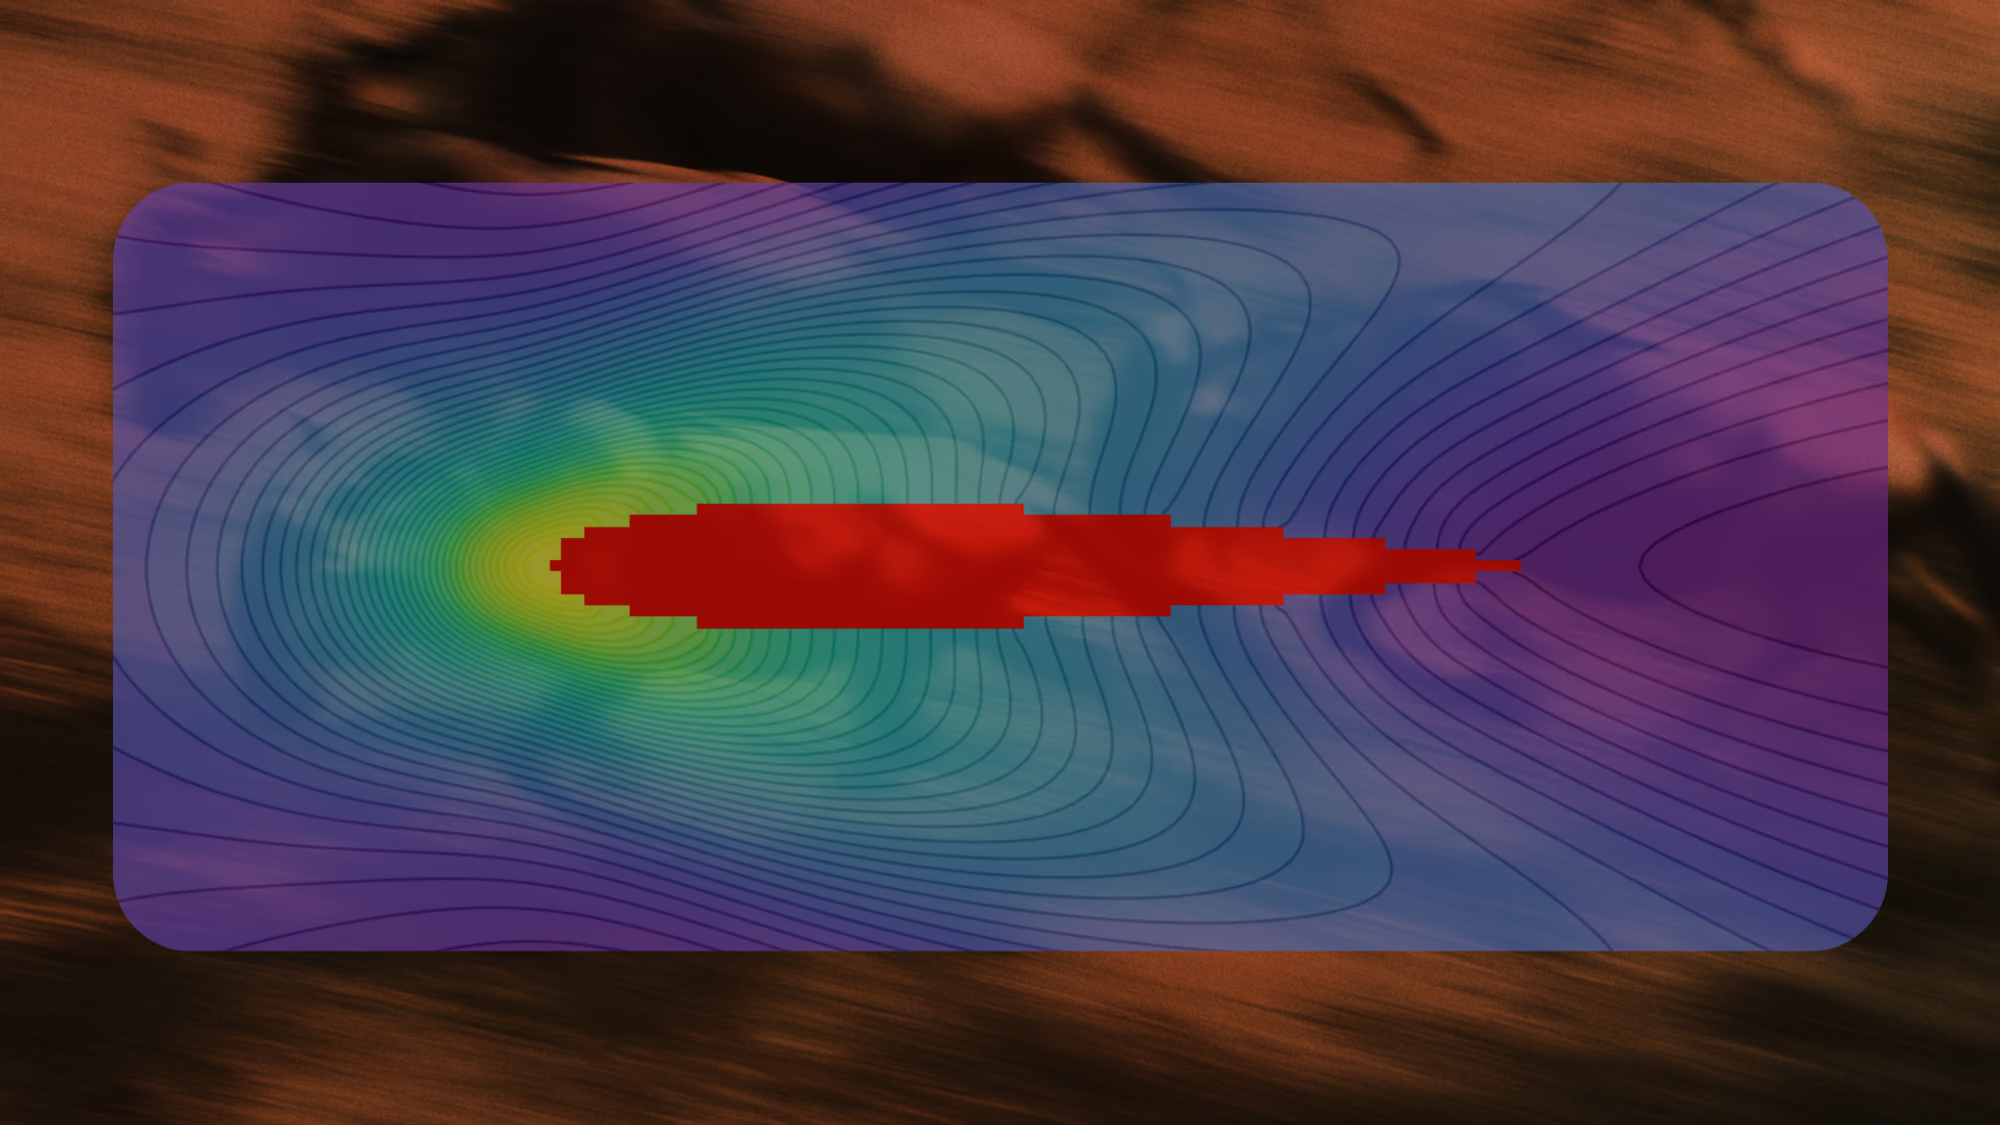

The pharmaceutical industry seeks drugs with high potency and precise selectivity to improve efficacy, reduce side effects, and lower late-stage failure rates. Targeted covalent drugs are especially promising because they form a specific, irreversible bond with a target protein via a reactive chemical group called a warhead. When properly tuned, this mechanism delivers exceptional potency and durability—aspirin being one of the earliest examples. The challenge is predicting warhead reactivity: higher reactivity generally improves potency, but excessive reactivity undermines selectivity. Accurately balancing this trade-off remains a major bottleneck in drug discovery.

With R&D costs exceeding $2B per drug, pharma increasingly combines machine learning and computational chemistry to accelerate discovery. A powerful approach uses first-principles calculations to generate “quantum fingerprints”—physically grounded features that improve reactivity prediction. However, classical simulation methods scale poorly: they rely on approximations that are either too inaccurate to capture critical many-body effects or too expensive for practical screening.

Quantum computing offers a solution, but until now has been constrained by hardware noise, limiting usable circuit depth to a few hundred two-qubit gates. Haiqu, working with Capgemini, IBM, and GSK, broke this barrier by demonstrating one of the largest electronic-structure Hamiltonian simulations ever run on real quantum hardware for covalent drug warheads. Using advanced circuit compression and middleware execution, the team initially reduced circuit depth by 15.5× and further allowed end-to-end execution by running sub-circuits up to 371 gates.

Collectively, these results establish a scalable, hardware-realistic path for running Hamiltonian simulations on larger active spaces, while maintaining sufficient accuracy for molecular reactivity prediction.